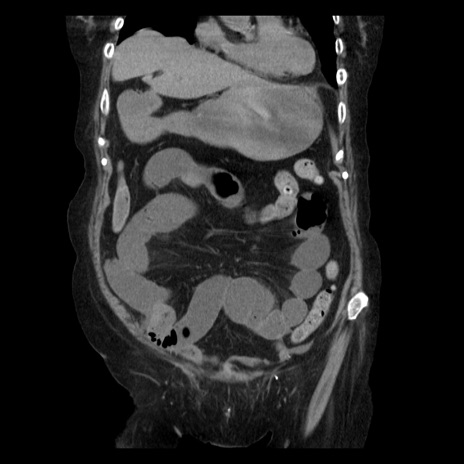

症例14(冠状断像)

【症例】 90歳代女性

【主訴】 腹痛・嘔吐

【現病歴】今朝から左側腹部痛を認めた。 経過観察していたが、嘔吐を認めたため来院。

【既往歴】 子宮癌術後

【身体所見】 意識清明、BP 127/54mmHg、P 98bpm Sp02 95%(RA)、BT 35.8°C、腹部平坦・軟腸ぜん動音聴取良好、右下腹部圧痛(+) 反跳痛なし

【データ】WBC 9800、CRP 0.46